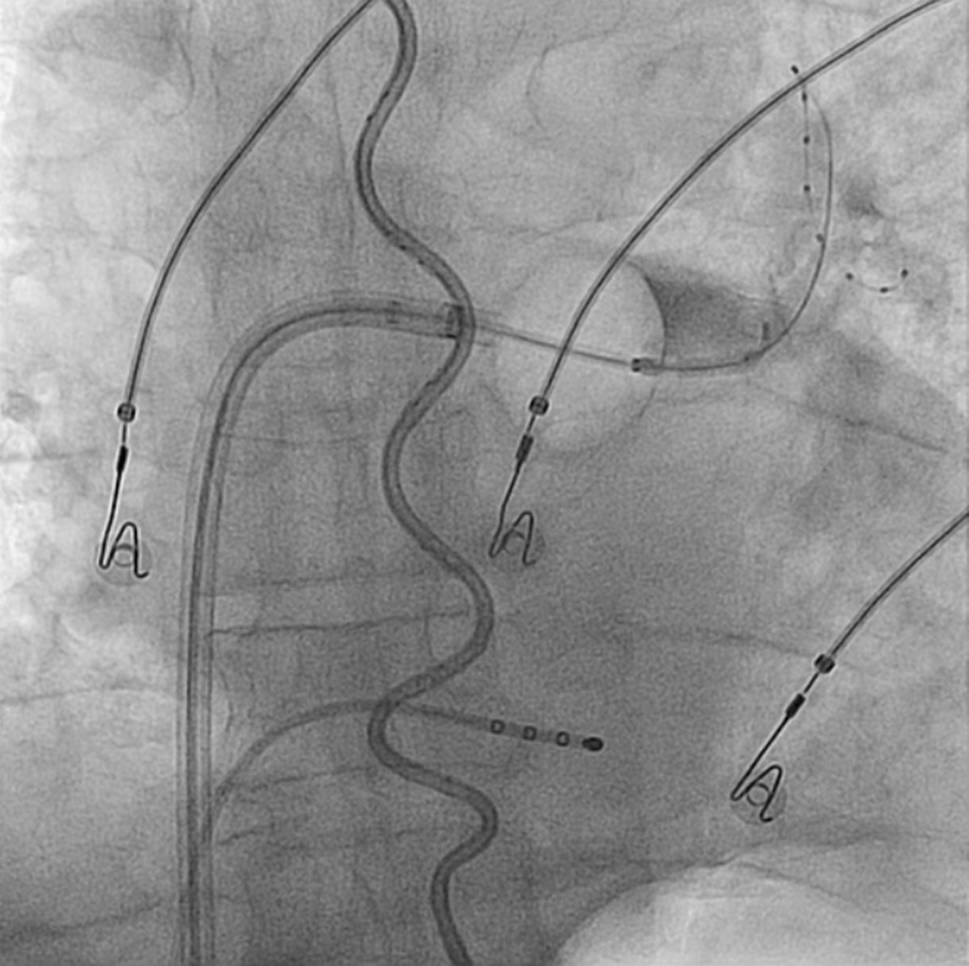

PVI procedure

Fig. 1

Position of the thermoprobe (S-shaped) in the oesophagus with cryoballoon positioned at the antrum of the left superior pulmonary vein with the lasso catheter inside this pulmonary vein and contrast dye being injected into the pulmonary vein (right upper quadrant). The stimulation catheter is positioned in the coronary sinus

During cryoablation of the right-sided PVs the right phrenic nerve was continuously stimulated by pacing from the superior cava vein or the right subclavian vein. If diminished diaphragm excursion was observed during cryotherapy, the application was stopped immediately using the double-stop technique [11]. If the OT reached <16 °C, the application was stopped prematurely [8]. No subsequent application was initiated until the OT reached >30 °C again.